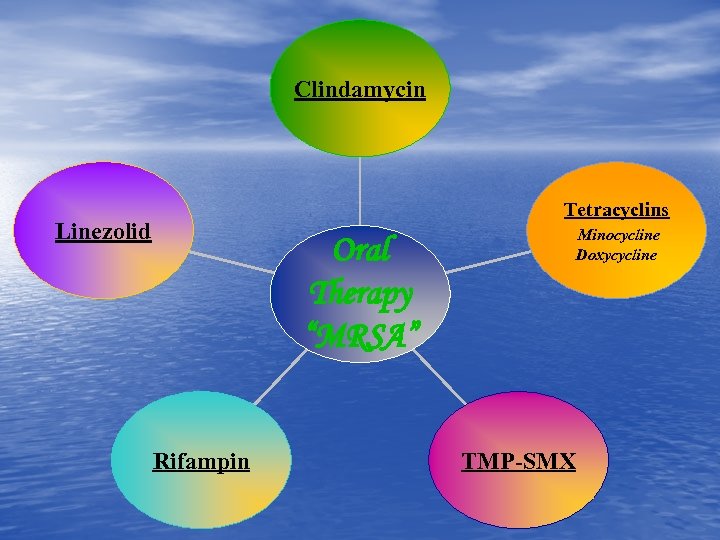

Clindamycin Linezolid Oral Therapy “MRSA” Rifampin Tetracyclins Minocycline Doxycycline TMP-SMX

Clindamycin Linezolid Oral Therapy “MRSA” Rifampin Tetracyclins Minocycline Doxycycline TMP-SMX